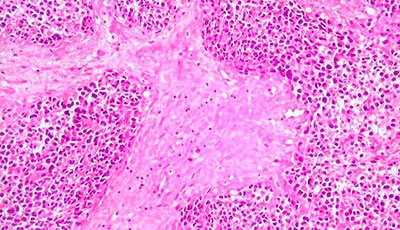

sarcoma_partes_moles_extremidades.jpgPesquisadores italianos, do Istituto Nazionale dei Tumori, em Milão, desenvolveram dois modelos de predição de risco para pacientes com sarcomas de partes moles de extremidades, validados para predizer sobrevida global e prever a ocorrência de metástases à distância. Os dados foram publicados no Lancet, em artigo de Dario Calegari e colegas.